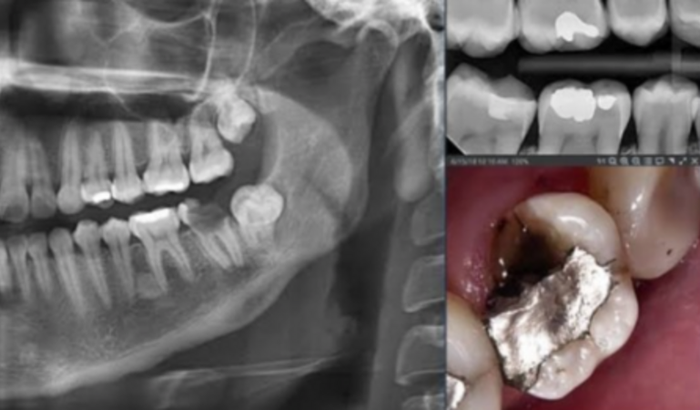

Oi sou conhecida dona derlete Cardoso que está precisando do valor R$2000,00 para custear seu tratamento odontológico ,ela tava esperando pelo sus mais ,está demorado muito ela não aguenta mas de dor de dente.. ela já fOi atrás de tratamento particular eo dentista passou o valor o tratamento que de R$ 2000,00..ela não tem condições de custear esse tratamento..vi através da vaquinha on line pedir essa a ajuda..